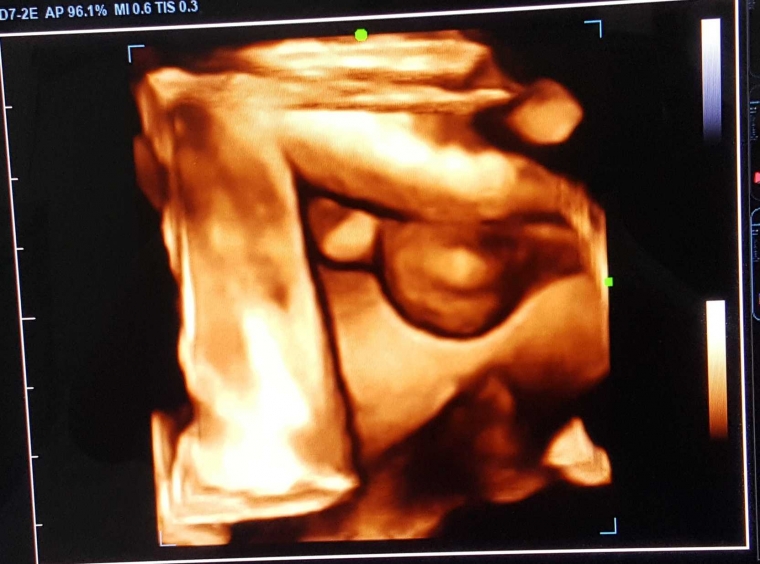

Contoh usg 4 dimensi. Jadi pasien dapat melihat lebih jelas dan membayangkan keadaan janin di dalam rahim. Jadi berupa live 3 dimensi. Usg 4 dimensi adalah jenis usg yang paling canggih dari semua jenis usg versi sebelumnya. Kondisi ini dibutuhkan saat dokter ingin mengamati perilaku janin fetal behavior lebih jauh. Jenis usg ini mampu menunjukkan gambar yang lebih detil sehingga dokter akan lebih mudah dalam mengidentifikasi masalah pada kehamilan. Contoh gambar 4 dimensi janin 5 bulan klik gambar dibawah ini.

Setiap jenis usg memberikan hasil yang berbeda beda. Teknologi 3d dirasa belum cukup karena tidak dapat merekam gerak janin secara real time. Gambaran usg 4 dimensi seperti menonton sebuah film yang bergerak. Hal penting sebelum melakukan usg 4 dimensi. Berikut beberapa contoh gambar 4 dimensi. Kalau gambar yang diambil dari usg 3 dimensi statis sementara pada usg 4 dimensi gambar janinnya dapat bergerak.

Jadi berupa live 3 dimensi. Berikut beberapa contoh gambar 4 dimensi. Seperti halnya penggunaan usg 4 dimensi dimana penggunaan usg 4 dimensi ini sangat membantu untuk mendapatkan objek dari calon anak yang akan terlihat perkembangannya dan biasanya akan terlihat lebih jelas daripada menggunakan usg 3 dimensi. Dibandingkan usg 2 dimensi dan 3 dimensi sekarang ini ada usg 4 dimensi. Selain foto yang saya peroleh saya juga mendapatkan videonya loooohhh untuk teman teman yang ingin tahu bagaimana hasil usg 4 dimensi yang berupa video silahkan download link dibawah ini.